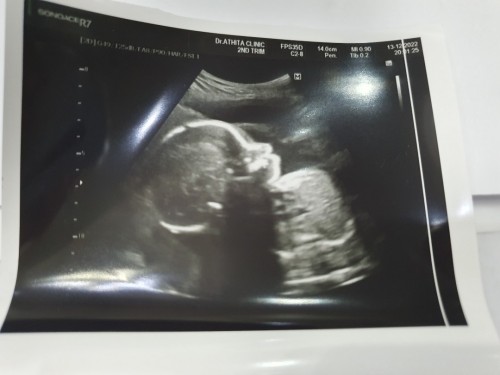

26 สัปดาห์

กำลังจะมีลูก